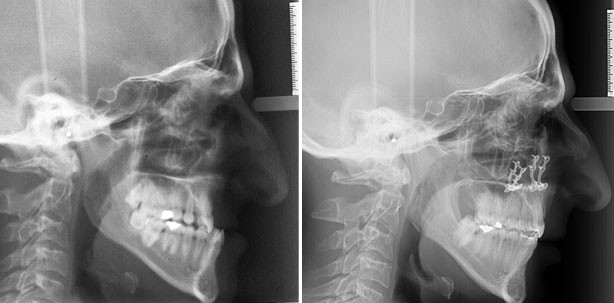

Die FRS-Aufnahme zeigt deutlich die Dysgnathie in der Sagittalen und Vertikalen sowohl im Weichteilprofil als auch im skelettalen Bereich (Abb. 4a und b). Die Parameter wiesen auf eine deutlich starke skelettale Dysgnathie: mesiobasale Kieferrelation, der ANB-Winkel betrug –8 °. Die vertikale Einteilung des Weichteilprofils zeigte eine leichte Disharmonie zwischen dem Ober- und dem Untergesicht (G’-Sn : Sn-Me’; 48 % : 52 %). Diese äußerte sich nicht so deutlich in den knöchernen Strukturen (N-Sna : Sna-Me; 44 % : 56 %). Diese Änderungen im Verhältnis lagen weniger in einer Alteration der Oberlippenlänge als vielmehr in einem verlängerten Untergesicht (Tab. 1).

Die FRS-Aufnahme zeigt die Änderungen der Parameter (Abb. 8a und b, Tab. 1). Aufgrund der operativen Impaktion der Maxilla haben sich alle Parameter in der sagittalen und vertikalen Dimension verändert.

Bei der vertikalen Einteilung des knöchernen und Weichteilprofils zeigt sich eine Harmonisierung. Das OPG (Abb. 9) zeigt die Situation nach Ende der Behandlung und vor der Entfernung des Osteosynthesematerials.